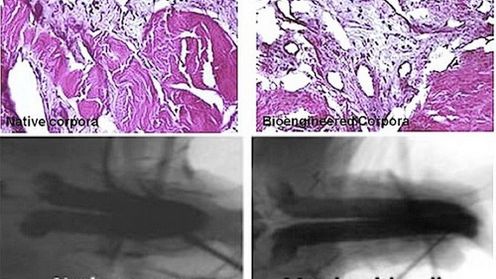

Może wyda się Wam to śmieszne (bo rzeczywiście takie jest!), ale to jest najprawdziwsza prawda. Oczywiście, nie chodzi o męskie przyrodzenia. Naukowcom udało się wyhodować królicze penisy. Rosa Golijan z Gizmodo, zastanawia się przede wszystkim, w jaki sposób zwierzątka straciły tą najcenniejszą część swojego ciała. Też mnie to zaintrygowało. Jeśli dokonali tego ludzie, to są naprawdę bez serca! A co, jakby eksperyment się nie udał? Ale nie to jest w tym momencie najważniejsze, bowiem wszystko skończyło się zgodnie z planem.

Naukowcy w próbówkach wyhodowali małe penisy, a następnie przeszczepili je króliczkom. Jak już wspominałem, wszystko się udało i sprzęt był w pełni funkcjonalny. Część zwierzaków została nawet tatusiami.

Naukowcy już przewidują, że w przyszłości możliwe będzie zrobienie tego samego w przypadku ludzi. Na pewno ucieszy to tych wszystkich, którzy stracili swoje klejnoty w nieszczęśliwym wypadku.